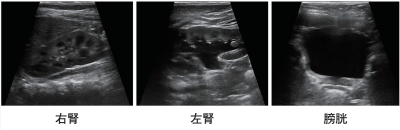

尿所見:淡黄色で混濁なし、蛋白(-)、潜血(-)、白血球(-)、亜硝酸(-) 。両腎と膀胱の超音波像を別に示す。腹部・骨盤腔内に占拠性病変は認めなかった。